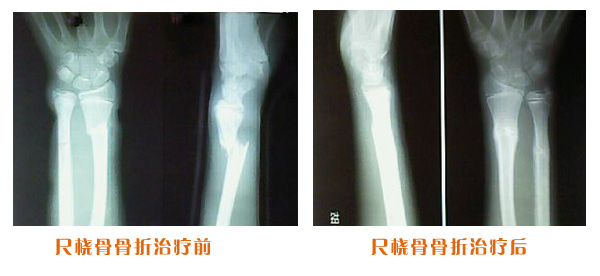

肥城市安駕莊梁氏骨科醫院是一所以梁氏手法正骨配合膏藥為特色的現代化??漆t院。

梁氏骨科術始創于清雍正年間,歷經八代,至今已有三百年歷史。據1929年泰安縣志載“梁瑞圖先生,字增生,號蓮峰,安駕莊人,精岐黃并發明接骨,凡跌打車凡跌打車軋皮不破而碎骨者......【詳細】 |